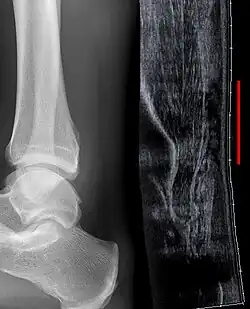

Achilles tendon rupture seen on ultrasound. Note discontinuity over several centimeters (red line). No fracture or avulsion (radiograph).

Ultrasonography can be used to determine the tendon thickness, character, and presence of a tear. It works by sending harmless high frequencies of sound waves through the body. Some of these sound waves reflect back off the spaces between fluid and soft tissue or bone. These reflected images are analyzed and created into an image. These images capture in real time and are helpful in detecting movement of the tendon and visualizing injuries or tears. This device makes it possible to identify injuries and observe healing over time. Ultrasound is inexpensive and involves no harmful radiation. It is operator-dependent and so requires a level of skill and practice for it to be used effectively.[16]

Radiography can also be used to indirectly identify Achilles tendon tears. Radiography uses X-rays to analyze the point of injury. This is not very effective at identifying soft tissue injuries. X-rays are created when high energy electrons hit a metal source. X-ray images are acquired by utilizing the different densities of the bone or tissue. When these rays pass through tissue they are captured on film. X-rays are generally best for dense objects such as bone while soft tissue is shown poorly. Radiography is not the best for assessing an Achilles tendon injury. It is more useful for ruling out other injuries such as heal bone fractures.[15]